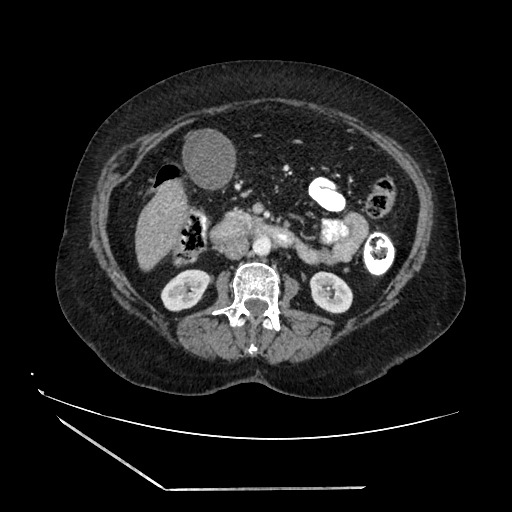

A 70 years old woman with Obstractive jaundice & palpable GB

Present

complaints:

Pain in abdomen

Fever

Headache

Vertigo

Yellowish eyes

Distension &

Tenderness of abdomen

Slightly in edema in both

legs

Nausea &

vomiting

Dullness

Loss of appetite

Constipation

Yellowish urine